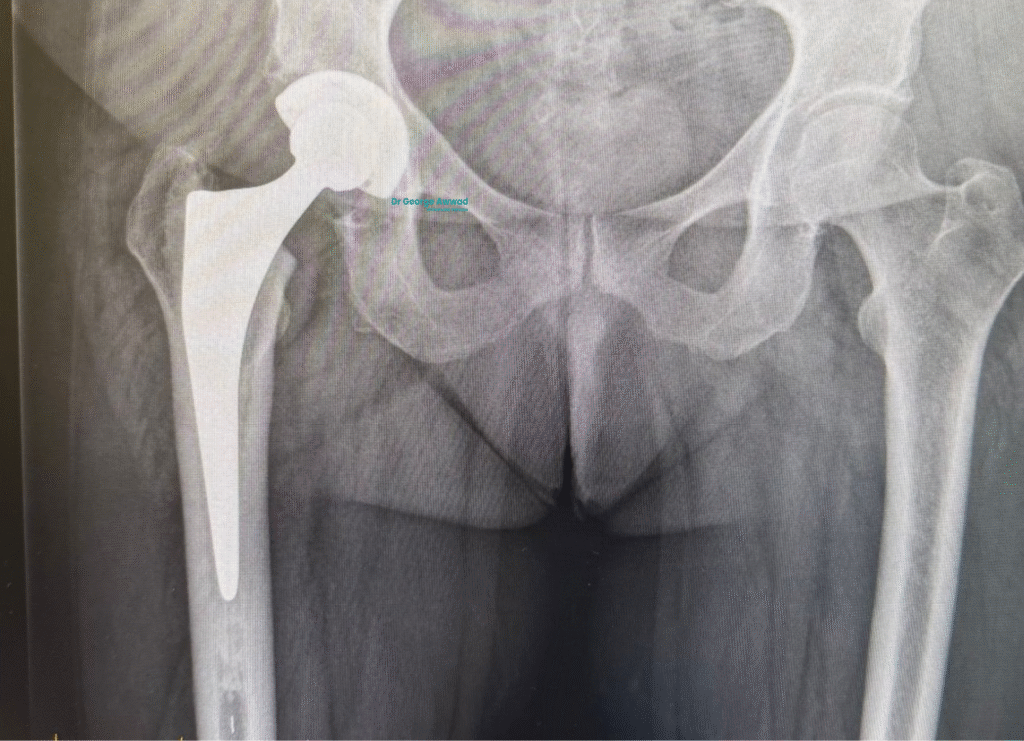

The role of imaging and surgical planning in hip replacement surgery

A well executed hip replacement begins with careful planning. Before entering the operating theatre, Dr George Awwad uses a combination of advanced imaging and digital planning tools to ensure your hip replacement is accurately tailored to your anatomy. This level of detail helps improve implant positioning, joint alignment, and long-term function.

Imaging used to assess your hip joint

The planning process typically begins with X-rays to assess joint space, bone structure, leg length, and the degree of arthritis present. In most cases, a CT scan is also arranged to provide a high resolution, three dimensional view of the hip joint and surrounding bone.